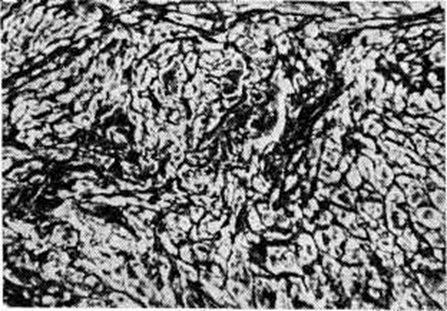

При гипертонической болезни исходным моментом развития Кардиосклероз является гиперплазия, содружественная с гипертрофией миокарда, и огрубение аргирофильного каркаса стромы (рисунок 1); в дальнейшем происходит формирование коллагеновых волокон и развитие диффузного миофиброза. Характерным для этого вида Кардиосклероз является также наличие в миокарде микроскопических рубчиков (цветной рисунок 2) вследствие гибели отдельных миоцитов или небольших групп их.

Миокардитический кардиосклероз — исход миокардитов (смотри полный свод знаний) инфекционно-аллергической, бактериальной или вирусной этиологии, сопровождающихся экссудативными и пролиферативными процессами в строме миокарда и деструктивными изменениями миоцитов. К этим процессам относится Кардиосклероз после перенесённого ревматизма, дифтерии, скарлатины, заражения Коксаки-вирусом или энцефаломиокардитическим вирусом, изредка вирусом полиомиелита или оспенной вакцинации; чрезвычайной редкостью является Кардиосклероз после туберкулёзного или сифилитического интерстициального миокардита. Миокардитический Кардиосклероз может носить характер диффузного миофиброза, локализующегося преимущественно в левом желудочке, и выражается в распространённом огрубении аргирофильной стромы миокарда и образовании коллагеновых волокон, что придаёт строме вид грубой решётки, в ячейках которой заключены отдельные мышечные волокна или группы их. Такой Кардиосклероз называют стромогенным. В случае же гибели небольших групп миоцитов возникают небольшие рубчики, или очажки Кардиосклероз. При диффузном ревматическом интерстициальном миокардите с мукоидной дезорганизацией стромы наблюдается диффузный интерстициальный миофиброз (цветной таблица, ст. 144, рисунок 3) и одновременно как исход ревматических гранулем около сосудов возникают овальные или звездчатые рубчики, являющиеся важным диагностическим признаком ревматизма (рисунок 2). Кардиосклероз (диффузный миофиброз) наблюдается также после аллергических миокардитов неясной этиологии (миокардита Фидлера, аллергического миокардита, описанного Я. Л. Рапопортом).

Кардиосклероз как следствие кардиомиопатий в большинстве своём неясной этиологии, развивается при болезни Фредерика, группе мышечных дистрофий, болезни накопления гликогена, гаргоилизме, семейной идиопатической болезни сердца, кардиомиопатии неясной этиологии ненаследственного характера (несемейная идиопатическая гипертрофия миокарда, застойная и гипертрофическая обструктивная кардиомиопатия, идиопатический эндомиофиброз и кардиомегалия жителей. Южной Африки), а также при кардиомиопатиях, связанных с недостатком тиамина и хронический отравлением кобальтом. В этих случаях Кардиосклероз носит характер диффузного миофиброза, иногда называемого заместительным миофиброзом: фиброзной тканью замещаются дистрофически изменённые, атрофирующиеся и гибнущие мышечные волокна (рисунок 3).